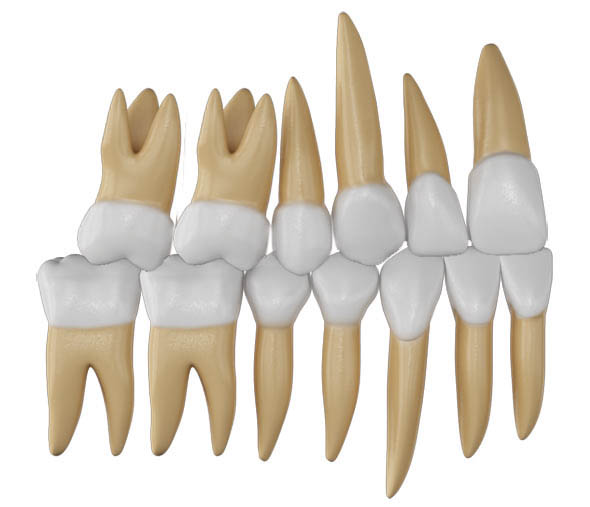

شکل 21-2: رابطه کلاسII مولری

شکل 22-2: رابطه کلاسII مولری